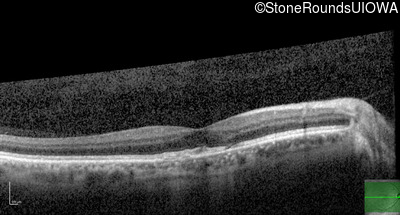

Optical Coherence Tomography - Right - 20/20 -2

Exemplar / OCT Stack